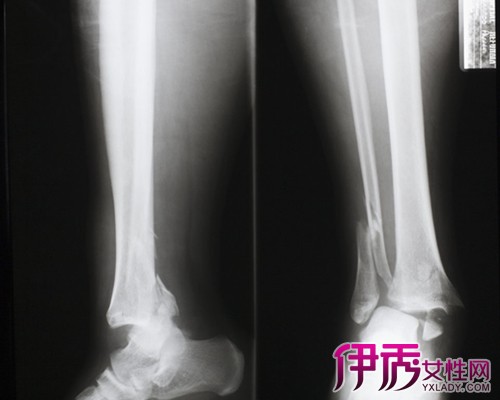

很多人在运动时,如果动作做得过大或是不规范,有可能造成骨裂在受到外力撞击时,也可能引起骨裂。如果是在运动中。骨裂大部分的位置会下肢骨骼,尤其是小腿。小腿骨裂症状一旦程度特别严重,有的可能还需要进行手术。骨裂在医学上有一个专业名称叫做裂纹骨折。

某些人认为的骨裂,实际上属于撕脱性骨折,它一般常见于打篮球中的跳起争球中,由指尖触球导致;还常见于运动前没有热身,就突然发力的跑、跳等。X线显示肢体中有一个极小的骨折碎片,一般不为患者重视。这种小的骨折碎片往往是韧带的附着点,它的移位意味着韧带的损伤。这种损伤一般都需要手术治疗,重建韧带的功能。

小腿骨折